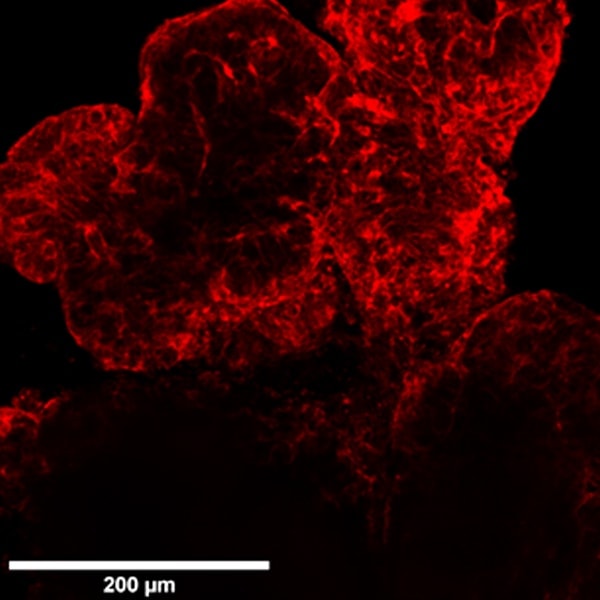

Here are shown organoids cultured in Matrigel on optical multi-well plates and generated from primary stem cells from colon cancer biopsies and stained for cytoskeleton by Phalloidin-568.

Comparison between Widefield, Confocal Spinning Disk and Super Resolution acquisitions.